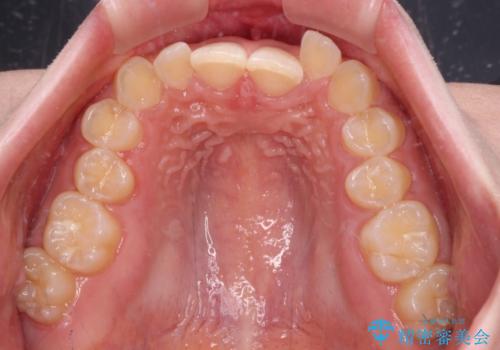

- 前歯のデコボコとディープバイトを気にして来院された患者様です。

左上前歯前方に飛び出しているため、歯列全体が前方に移動している状態でした。

短期間で確実に仕上げたいとのことで、アンカースクリューと補助装置を併用して歯列の後方移動を図り、ワイヤー装置にて矯正治療を行うこととしました。

左上の歯列は補助装置により速やかに移動し、1年程度で奥歯の咬み合わせが改善され、1年3ヶ月の短期間でしっかりと仕上げることができました。